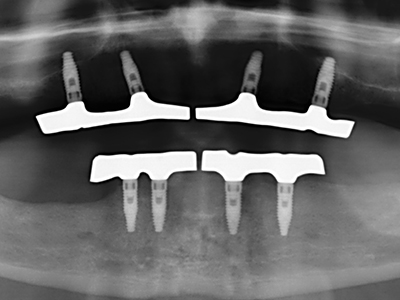

Quando le procedure chirurgiche vengono eseguite sull'osso nelle immediate vicinanze di strutture sensibili, come vasi sanguigni o nervi, gli strumenti rotanti pongono un rischio significativo di lesione iatrogena. I dispositivi piezoelettrici possono essere utili per la preparazione delle coperture ossee e la rimozione del tessuto duro in prossimità dei nervi, in particolare per la loro esposizione dopo una lesione iatrogena, ma anche durante la lateralizzazione dei nervi per le procedure di resezione e ricostruzione o il posizionamento di impianti (figg. 17-20). Il contatto leggero tra puntina piezoelettrica e nervo non causa generalmente danni, ma se si procede senza prestare attenzione con movimenti a sega o raccordi con residui di substrati ossei possono verificarsi danni al nervo temporanei o anche permanenti. Il rischio di danno, tuttavia, è considerato sostanzialmente inferiore al rischio presente utilizzando seghe o frese (Pereira, Gealh et al. 2014).